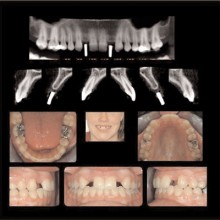

IMPLANTS: Implants that are used to replace missing teeth, for anchorage to mobilize teeth, or dental segments and, in some cases, can be restored to optimize function and esthetics. Implants need to be located where they will have the best chance for success. Prosthetic, anatomic, and biomechanical requirements independently or in combinations are key considerations to be resolved. Three-dimensional imaging techniques can play a significant role revealing the anatomic considerations and linking them to the prosthetic and biomechanical treatment options (Figures 5, 6).

ORTHODONTIC RECORDS: The greatest recent innovation has been the inclusion of the spatially true-size three-dimensional digital image data into the orthodontic records. Ultimately the three-dimensional records will replace the two-dimensional records. The current generation cone beam CT promises to produce, in a single scan, enough information to eliminate the need for conventional panoramic, occlusal, cephalometric, selected periapical, and tempormandibular-joint tomographic studies and possibly plaster dental models. The CBCT data will be superior to that gained from the compiled series of two-dimensional images, and the absorbed dose will be less.

With the traditional two-dimensional dental-imaging series some areas of anatomy are poorly visualized. These three-dimensional scans can give valuable information about other areas of the dentition such as the position of the upper incisor roots relative to the lingual cortical border of the palate to plan retraction, the amount of bone available in the posterior maxilla available for distalization, the amount of bone lateral to the maxillary buccal segments available for dental rather than skeletal expansion, airway information on the pharynx and nasal passages, upper root proximity to the maxillary sinus, the three-dimensional extent of an atrophied alveolar ridge, or the position of the lower incisor roots in bone. These scans also allow three-dimensional visualization of bony defects and supernumerary teeth in patients with cleft lip and/or palate. Additionally, axially corrected tomograms of the temporomandibular joints can be obtained from the same scan. The ability to visualize an axially corrected view of the temporomandibular joints with the teeth in occlusion on the same reconstructed section is one significant advantage of the volume scan. Therefore, there is substantial “value-added” imaging benefits to these scans for complicated orthodontic patients.